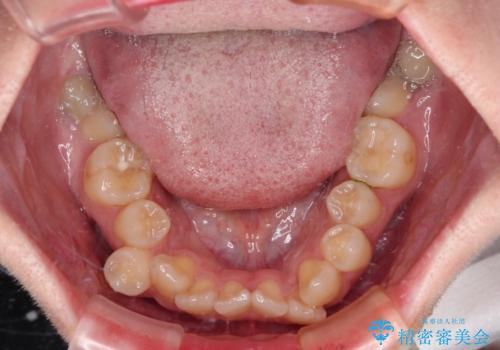

デコボコだらけの歯列をきれいに ワイヤー装置での抜歯矯正治療

- 上下前歯のデコボコを気にして来院された患者様です。

口元の突出感はあまりなかったものの、デコボコを非抜歯で改善すると出っ歯になる可能性があるため、上下左右の第一小臼歯4本を抜歯し、ワイヤー装置にて矯正治療を行うこととしました。

口元の突出感はなかったものの、捻転や八重歯を改善するために補助装置を併用する必要がありました。